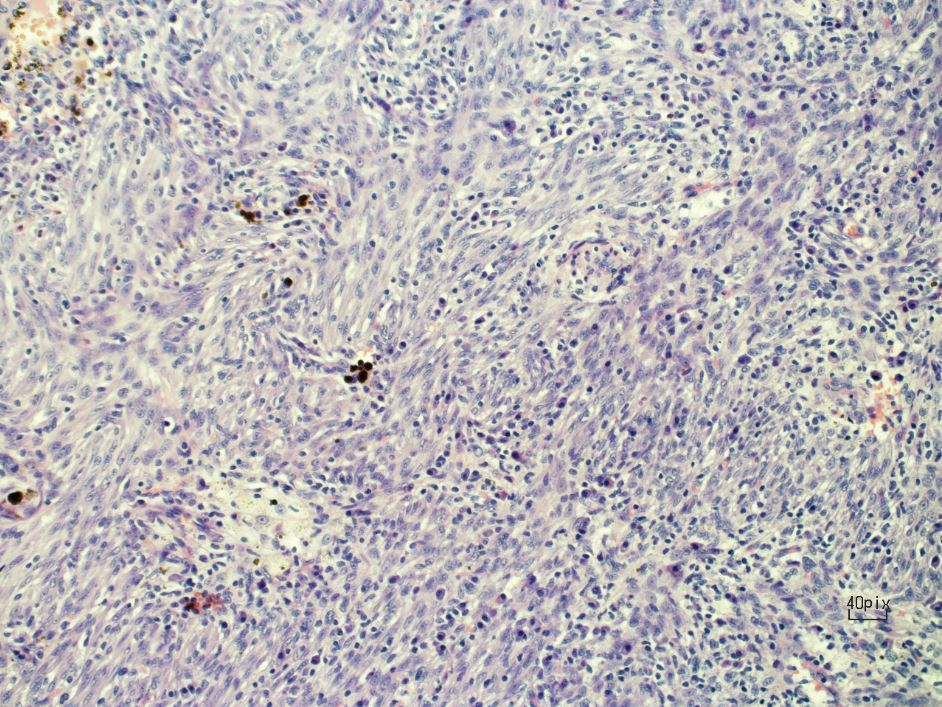

Figure 3. Bland-looking spindle cells.

Inflammatory myofibroblastic tumors (IMT) were first observed and described by Bunn in 1939, and were later named by Umiker and colleagues. IMTs are a rare type of lesion that affect different anatomical locations of the body, and they make up 0.7% of tumors in the lung, parenchyma, and bronchus (1). An IMT usually presents as a solitary nodule but can also present as a locally invasive lesion. Pathologically, IMTs are identified by a proliferation of spindle cells associated with a variably dense polymorphic infiltration of mononuclear inflammatory cells.